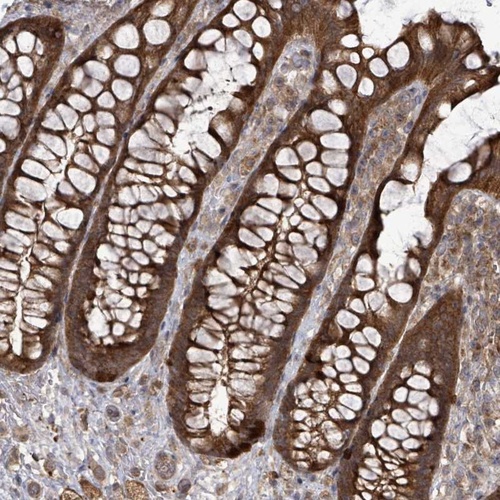

Immunohistochemical staining of human rectum shows strong cytoplasmic positivity in glandular cells.